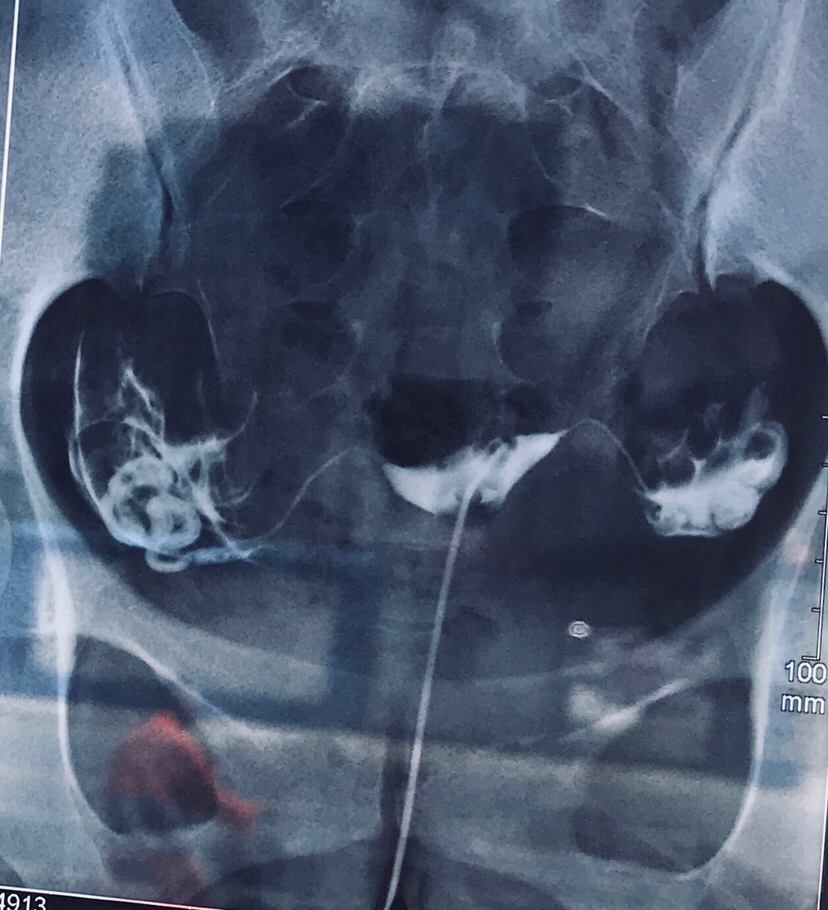

备孕中

孕10周+2天

不用做了,做了还是会粘连的,还疼

备孕 不孕不育